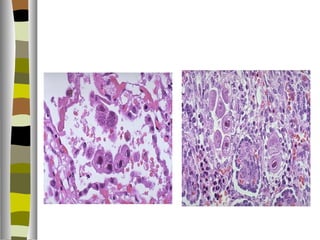

Amebiosis

   Entamoeba histolytica

   Países en vías de desarrollo

   Disentería y absceso hepático

   Forma infectante son los quistes ( resisten ácido gástrico ) y en el

lúmen intestinal liberan los trofozoítos ( forma ameboide ) que lisa las

células epiteliales e invade la pared intestinal

   Compromete ciego/ colon ascendente / recto / apéndice

   Crean úlceras de base amplia con un cuello delgado

   Un 40% de pactes con disentería amebiana, los protozoarios alcanzan

los vasos porta y embolizan al hígado produciendo abscesos

   Abscesos hepáticos con poca inflamación en los márgenes y

hemorragia en las cavidades, se llenan de un material achocolatado

poco oloroso, da distensión de la cápsula hepática y dolor. Se dx. Por

U.S.